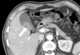

Small gallbladder

In vertebrates, the gallbladder is a small hollow organ where bile is stored and concentrated before it is released into the small intestine. In humans, the pear-shaped gallbladder lies beneath the liver, although the structure and position of the gallbladder can vary significantly among animal species. [Source: Wikipedia ]